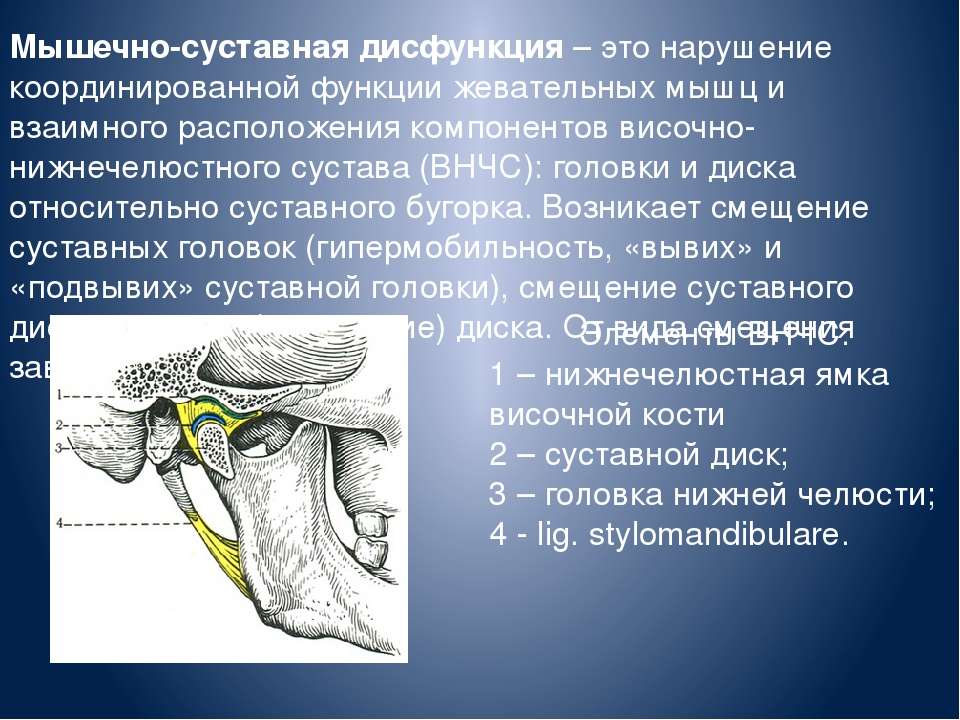

Дистрофические заболевания внчс презентация - 89 фото